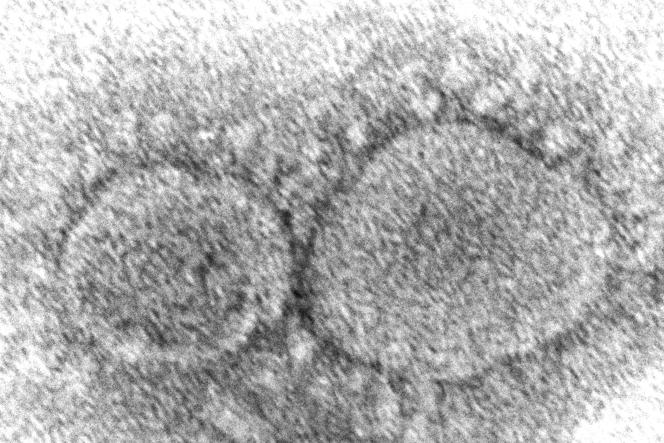

Covid-19 : le variant Omicron peut contourner les défenses vaccinales

Omicron, avec sa cinquantaine de mutations, va-t-il mettre en péril la stratégie vaccinale en cours de déploiement face à la pandémie ? Les premières études expérimentales le font craindre : plusieurs d’entre elles montrent un affaiblissement de la protection immunitaire offerte par les vaccins face à ce variant, alors que les cas de réinfections ou d’infections de personnes déjà vaccinées se multiplient.